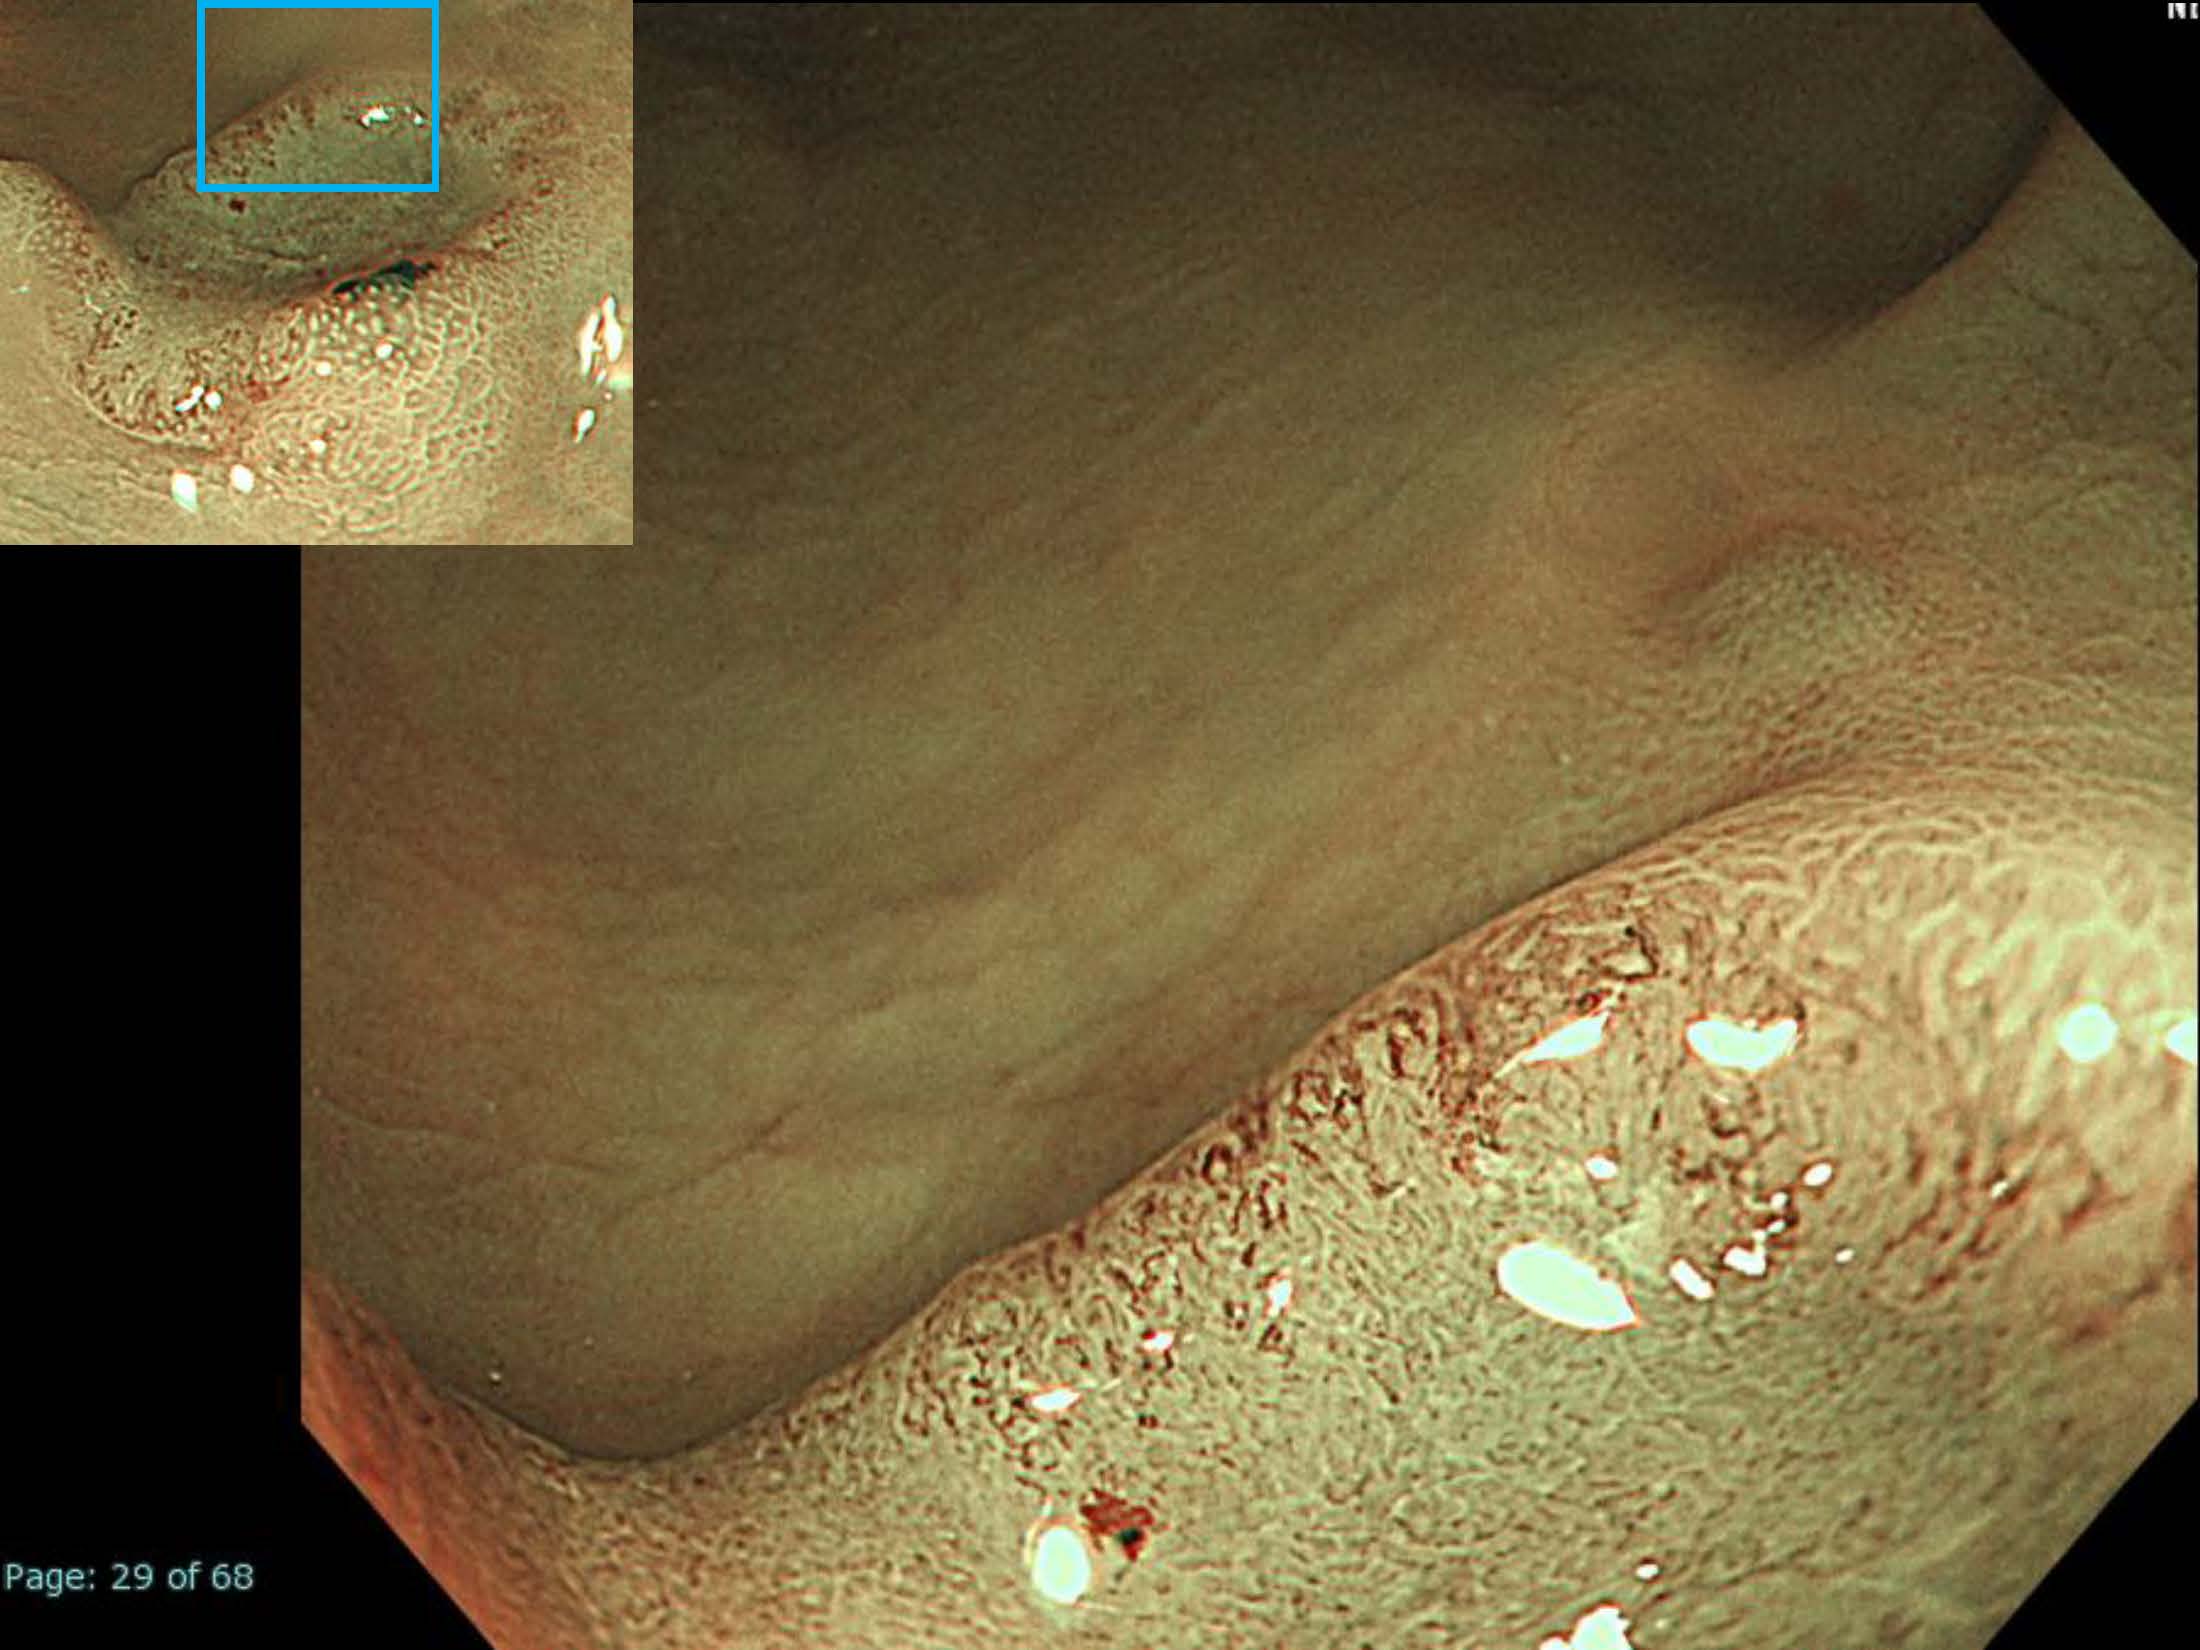

消化管Mapping~大腸~ 2021.10.27

消化管Mapping~大腸~

消化器内科

内視鏡検査・治療

消化管Mapping